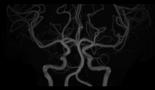

頭部MR検査

造影剤を使用しなくても血管の形態を描出することが可能です。